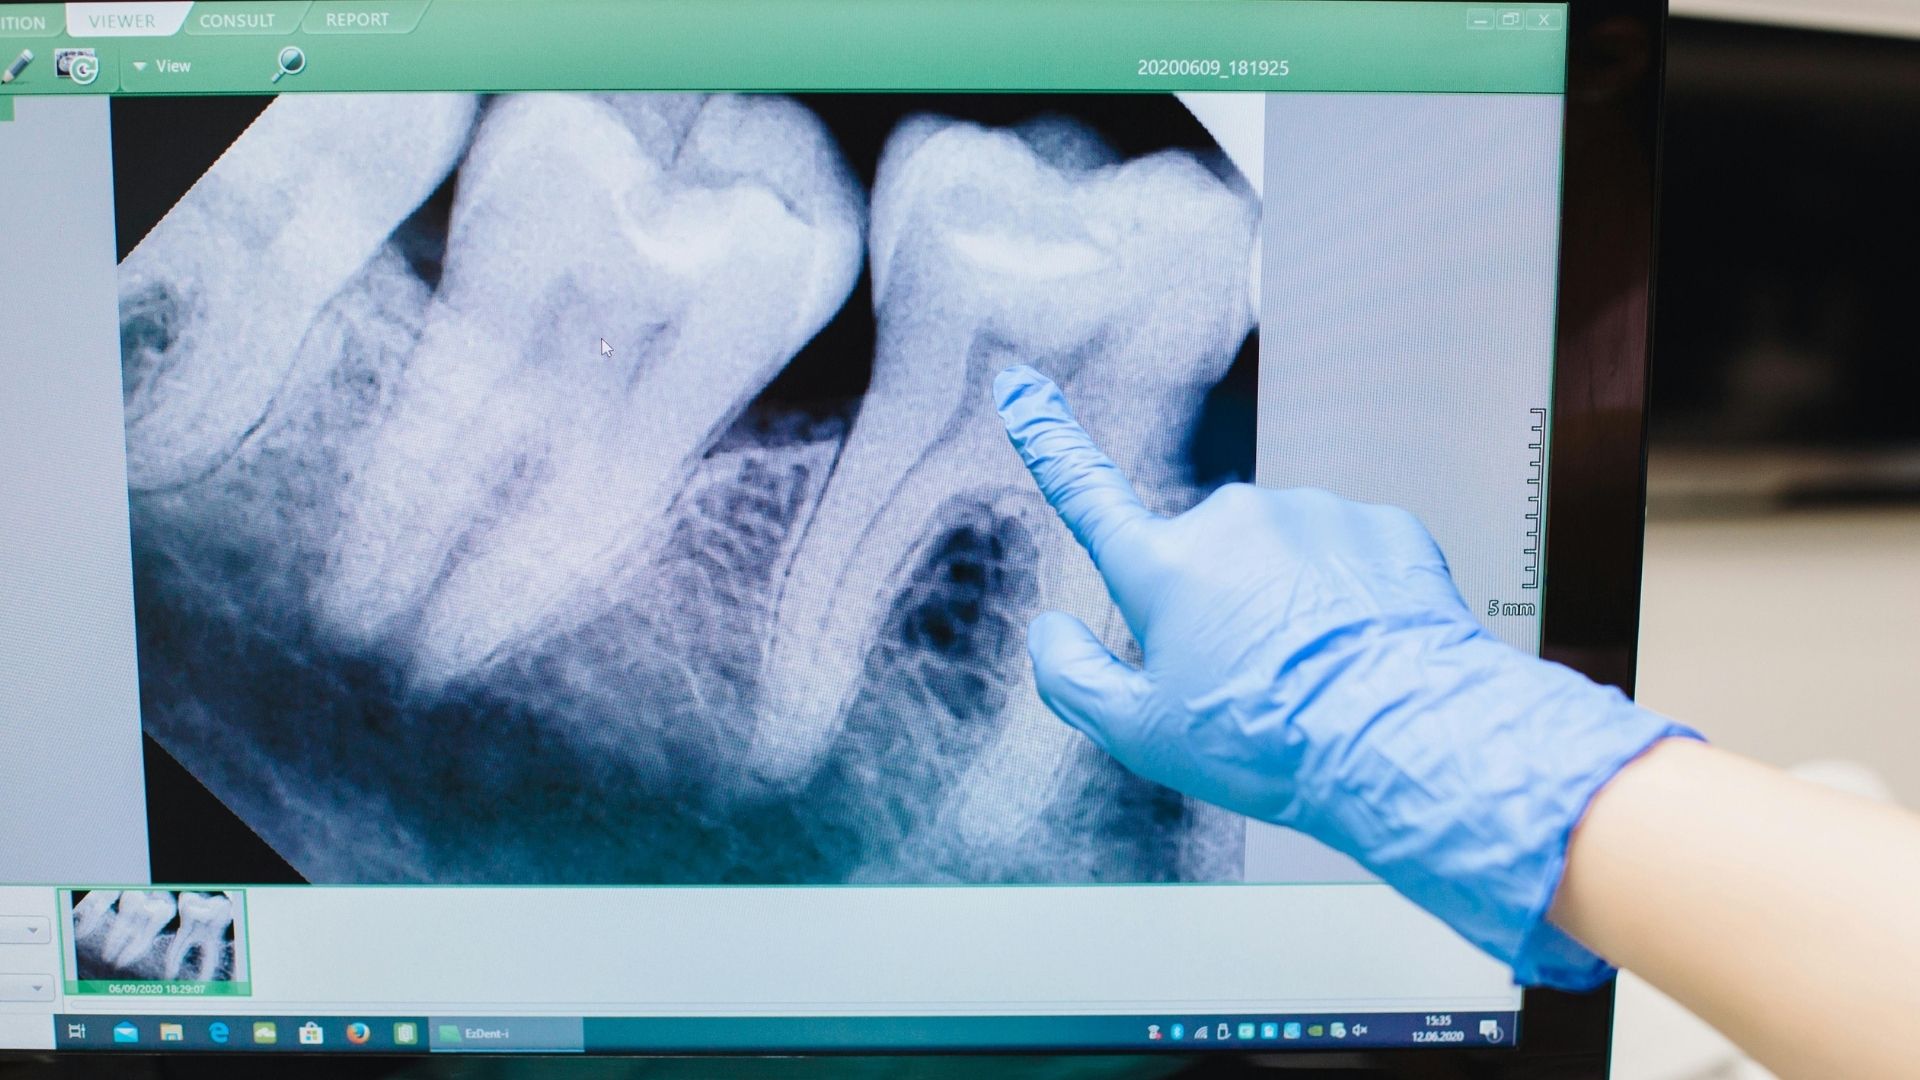

- Chụp X-quang quanh chóp: Giúp phát hiện tổn thương tủy, tiêu xương quanh chân răng hoặc áp xe.